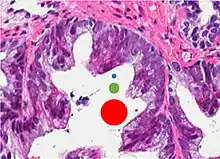

| Acinar adenocarcinoma - 93%[2] | Adenocarcinoma (not otherwise specified/ conventional/ usual acinar)[3] |

77%[notes 2] | 54%[notes 2] | ![]() |

Further information in section below

|

Tumorous glands: | As usual |